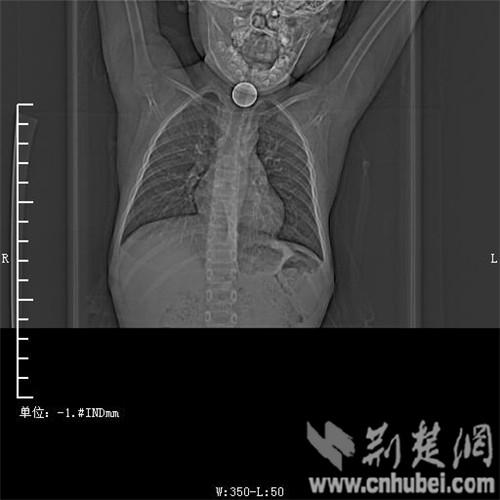

圖為:硬幣卡在了陽陽的喉部

消化內(nèi)主任方向明告訴記者,孩子送來時已經(jīng)是晚上8點15分,醫(yī)護人員立即給孩子拍胸部CT確定硬幣的位置,8點30分,方向明通過胃鏡下食管異物取出術,成功的將這枚一元硬幣取了出來。1月5日上午,陽陽順利出院,醫(yī)生護士在他出院時不斷告訴他,以后千萬不要吞含異物。